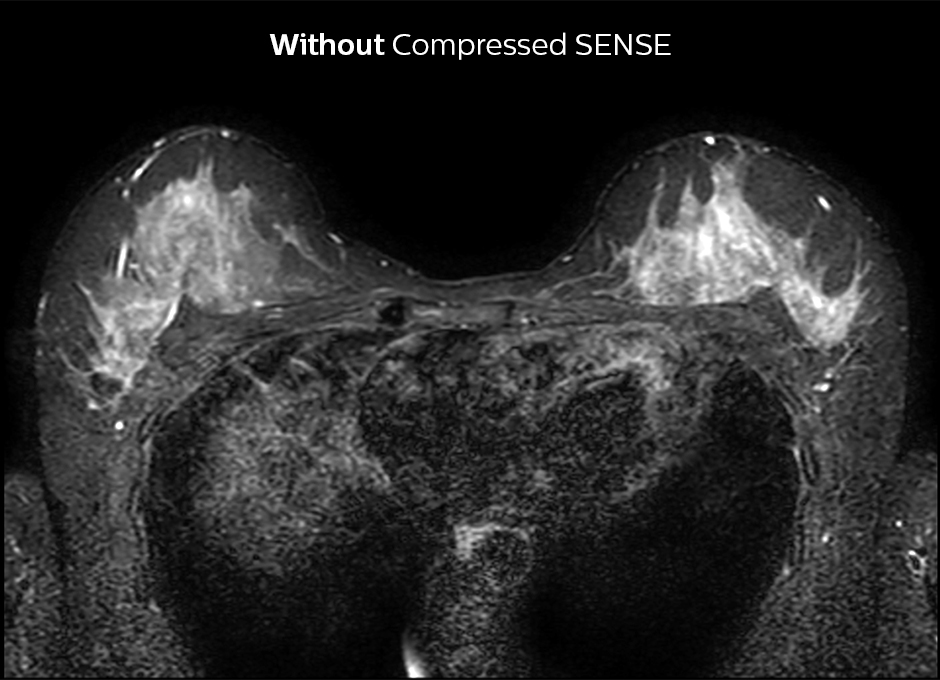

At KSW, Compressed SENSE is also applied to reduce scan time for breast imaging. 2D STIR is now faster and silicon-only sequences are 30% faster, for example. The post-contrast 3D T1 THRIVE can be accelerated by approximately 40% and Compressed SENSE is currently being added to the dynamic T1 sequence, where the goal is to get higher resolution in the same scan time.

2D STIR, scan time 3:39 min, voxel size 1 x 1.25 x 3 mm.

2D STIR, scan time 2:36 min, voxel size 1 x 1.26 x 3 mm.